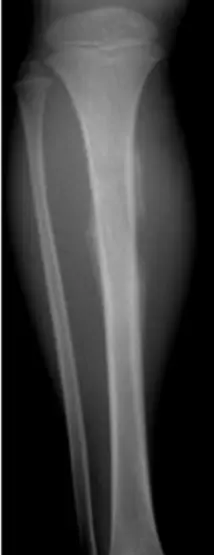

| Look | Compare both limbs, Skin, Muscle bulk, bony landmarks, hair distribution | Assess symmetry, signs of trauma, inflammation, muscle atrophy, structural changes | Visual examples - Skin, Muscle, Bone, Joint: ![]() ![]() ![]() ![]() ![]() ![]() | Swelling, scars, discoloration, hair changes, muscle wasting, bony protrusions, angulation, redness |

| Flexion & Extension (Normal: Extension: 0° → Flexion: 140°) | Quantify the knee’s range of motion | Extension: Flexion: ![]() | Reduced or excessive range of motion; “lacks X degrees of extension” | |